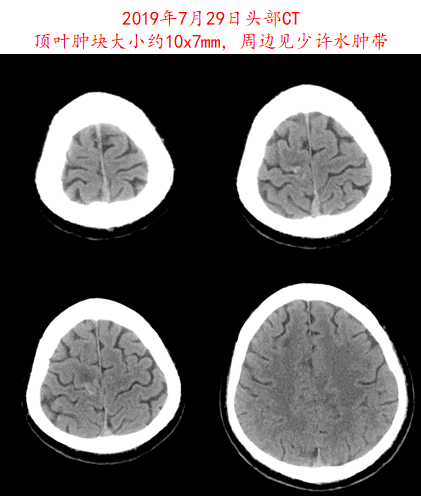

image007.png

图5.患者2019年7月29日头部CT影像资料